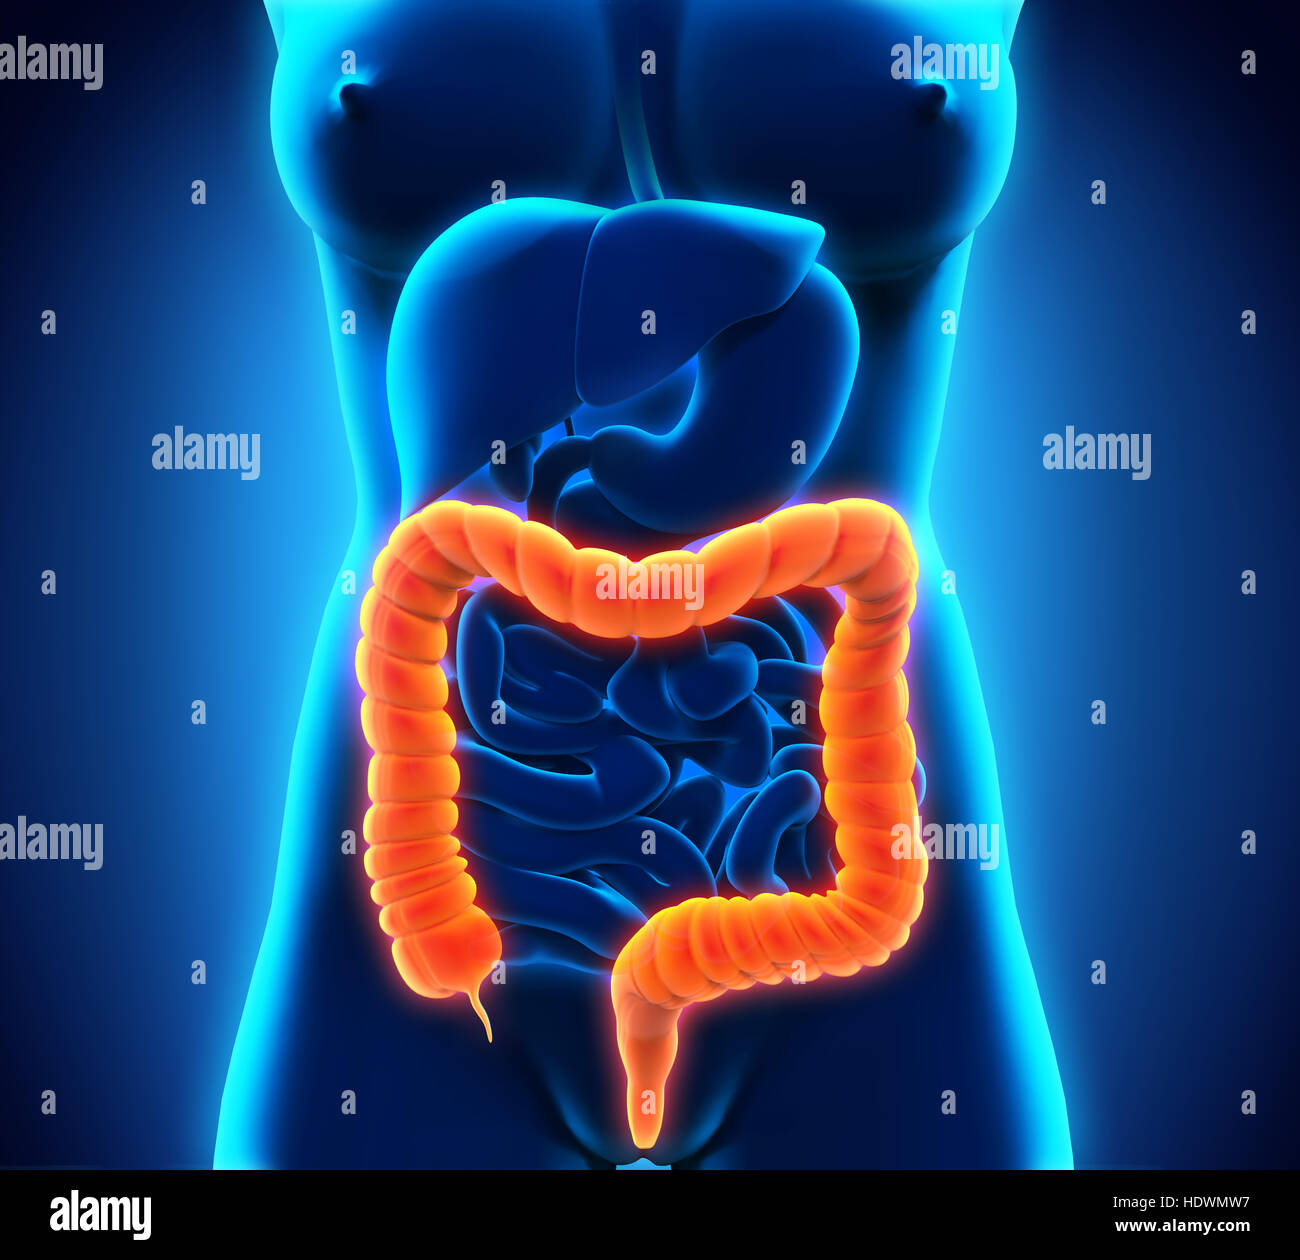

Colon humain anatomie Banque D'Imageshttps://www.alamyimages.fr/image-license-details/?v=1https://www.alamyimages.fr/photo-image-colon-humain-anatomie-129038117.html

Colon humain anatomie Banque D'Imageshttps://www.alamyimages.fr/image-license-details/?v=1https://www.alamyimages.fr/photo-image-colon-humain-anatomie-129038117.htmlRFHDX5C5–Colon humain anatomie